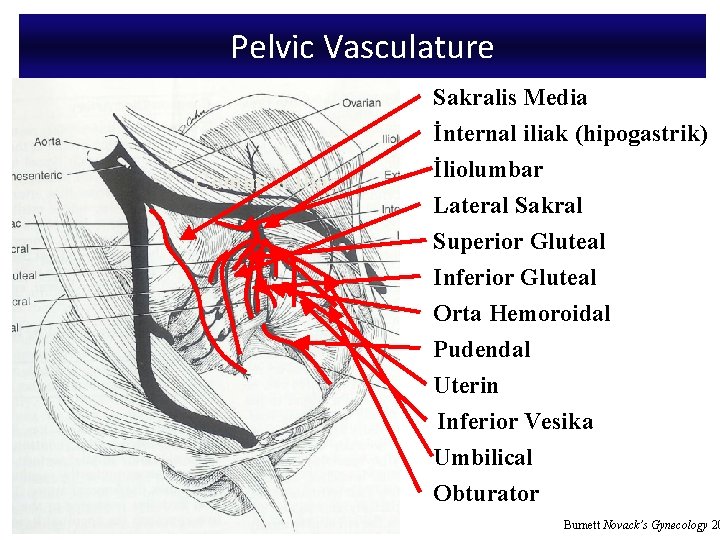

Pelvic Vasculature Sakralis Media İnternal iliak (hipogastrik) Common Iliac İliolumbar Lateral Sakral Superior Gluteal Inferior Gluteal Orta Hemoroidal Pudendal Uterin Inferior Vesika Umbilical Obturator Burnett Novack’s Gynecology 20

Branches of the Internal Iliac Artery Anterior Division Posterior Division Uterine Umbilical Uterine vesical Obturator Internal pudendal Inferior gluteal Middle vesical Middle rectal Vaginal Superior gluteal Lateral sacral Iliolumbar

Collateral Arterial Circulation of the Pelvis Primary Artery Aorta Ovarian artery Superior rectal artery (inferior mesenteric artery) Lumbar arteries Vertebral arteries Collateral Arteries Middle sacral artery Lateral sacral artery External Iliac Deep iliac circumflex artery Inferior epigastric artery Iliolumbar artery Superior gluteal artery Obturator artery Femoral Medial femoral circumflex artery Lateral femoral circumflex artery Obturator artery Inferior gluteal artery Superior gluteal artery Iliolumbar artery Uterine artery Middle rectal artery Inferior rectal artery (internal pudendal) Iliolumbar artery